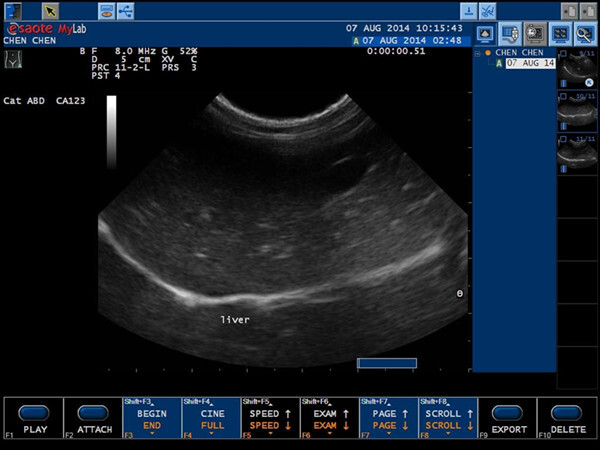

圈圈8/6送院時,醫生先幫牠驗血,發現牠有愛滋,第一次的檢查結果是:1.病毒感染,繼發全身細菌感染 ,球蛋白過高(超過三萬),口炎及爛牙嚴重,必須拔掉爛牙。2.有嚴重脫水。3.超音波檢查,腎有比較大顆但功能正常,泌尿道也沒有太大問題。4.X光檢查呼吸道沒有太大問題,但肝有寄生蟲移行後及明顯慢性䊹維化的症狀。8/14圈圈出現下痢,可能跟作了體內驅蟲有關。經過十幾天的治療,症狀都有較緩解,但到了8/20圈圈突然嘔吐,食慾也下降,醫生再度幫牠驗血發現白血球上升。9/3不肯進食,檢查發現口炎再度復發。動物近況說明: 經過將近一個多月的治療,圈圈的口炎、精神及食慾現在都已慢慢的恢復,目前也安排了一位中途朋友暫時在照顧牠。